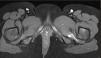

Debido a la sospecha de infección musculoesquelética, se inició tratamiento antibiótico intravenoso (cefuroxima y flucloxacilina), manteniendo a la paciente en reposo, con resolución de los síntomas. La resonancia magnética pélvica reveló «edema muscular difuso bilateral de los cuádriceps femorales, compatible con síndrome de pinzamiento isquiofemoral» (fig. 1), suspendiéndose el tratamiento antibiótico. En una entrevista posterior, la madre refirió que, el día previo al inicio de los síntomas, la paciente había subido y bajado repetidamente varias escaleras y plataformas en un parque infantil.

Este síndrome es el resultado de impactos sucesivos que provocan un estrechamiento del espacio isquiofemoral, que a su vez provoca inflamación y edema musculares1,2. La gravedad clínica no siempre se correlaciona con los hallazgos de la resonancia magnética. Es poco frecuente en la población pediátrica, y a menudo se pasa por alto en el diagnóstico diferencial del dolor de cadera. Aunque la miositis infecciosa es más frecuente a esta edad, en este caso se consideró poco probable debido a la presencia de un único episodio febril, la ausencia de afectación sistémica, los marcadores inflamatorios normales (incluyendo el recuento de leucocitos y los niveles de proteínaC reactiva y procalcitonina) y la ausencia en la resonancia magnética de hallazgos sugestivos de miositis infecciosa como licuefacción, necrosis o edema muscular extenso. El tratamiento de este síndrome suele ser conservador (reposo y antiinflamatorios no esteroideos), con un pronóstico favorable1,2.